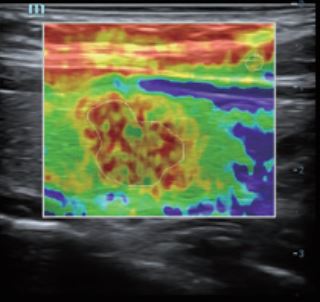

Natural Touch Elastography - Софтуер за ехограф Mindray